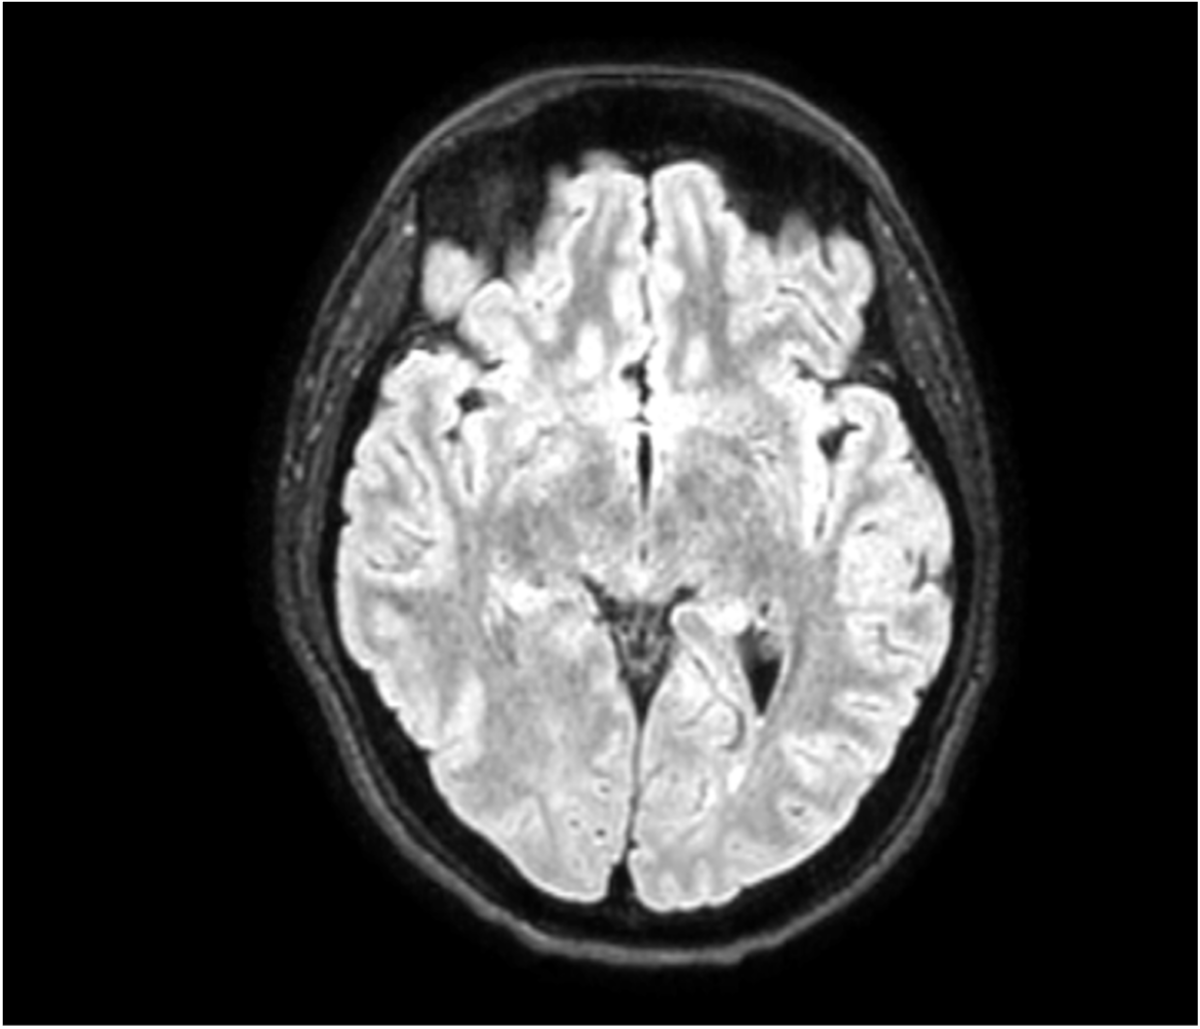

Open-Lip Schizencephaly in Adulthood

Joana Freitas Ribeiro, Cátia Gorgulho, Ana Matos

bjcr61